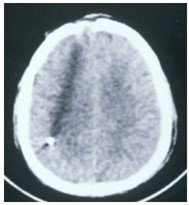

A case series from Amirjamshidi et al14 reported long-term follow-up data on 99 patients of 191 victims of the Iran-Iraq conflict who were treated at two centers affiliated with Tehran University of Medical Sciences.15 These patients ranged in age from 13 to 55 years and all were male. Patients received no initial surgical interventions for pTBIs obtained in battlefield areas due to shrapnel and shell fragments. Patients who had a GCS score of 8 or higher, no rapid deterioration in consciousness, and a small entrance wound of less than 2 to 3 cm were candidates for local treatment. Patients were treated with wound cleaning, local debridement, stitches, and dressing at a field hospital. They were then transferred to a medical center where better X-rays and computed tomography (CT) scans were taken and cases were reviewed by the attending surgeon. Sixty-two cases had CSF leakage, or the wound was under tension, requiring more superficial debridement of the skin, bone, and any contused brain tissue; however, the attending surgeon determined more extensive debridement was not necessary. Patients were then admitted, treated with antibiotics for 2 weeks, and had at least two additional CT scans. Mean follow-up was almost 8 years, in which time 91% of patients had good outcomes and were able to perform their usual job/activities, 4% were severely disabled, and 5% had died of their injuries or meningitis. None of the patients had brain abscesses, epilepsy, or hematomas. Outcomes were not significantly different for the 37 patients who did not require additional superficial debridement after transfer compared with the 62 patients who did.

In a another series reported by Taha et al6, 32 patients from conflict zones in Lebanon with shrapnel (84%) or gunshot injuries (16%) were treated within a mean of 3 hours after injury6, in an emergency room, with superficial entry wound debridement and wound closure without drainage. Patients had to have a GCS greater than 10, an exam within 6 hours of the injury, a small entry wound, no exit wound, and to meet other criteria related to missile tract and hematomas (Table). Patients ranged in age from 3 to 51 years with a mean age of 32 years. Most (19 of 32) patients had an initial GCS of 15. At follow-up (mean 3.5 years after injury) there were no deaths and no neurological deficits. Only one patient (3.1%) had complications including a seizure and then a brain abscess that was excised; however, 2 months later the patient had no abnormalities.